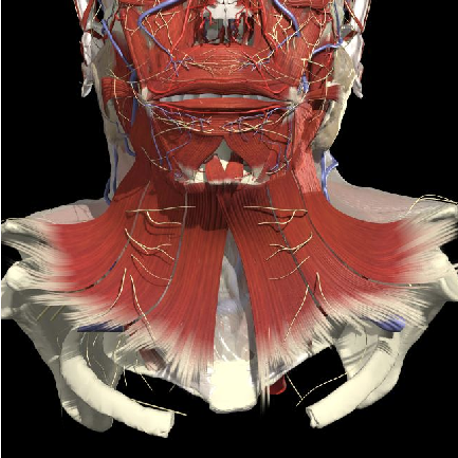

Structures to Avoid

Nerves in Posterior Triangle

Accessory nerve

Inject levator above this point

Landmarks

Cervical plexus

Midpoint of SCM (EP)

Middle and lower third of Trapezius

Arteries

Midpoint anterior border of SCM

Vertebral artery

- Occipital bone or C2 towards midline is safe

Occipital artery

Avoid apex of posterior triangle